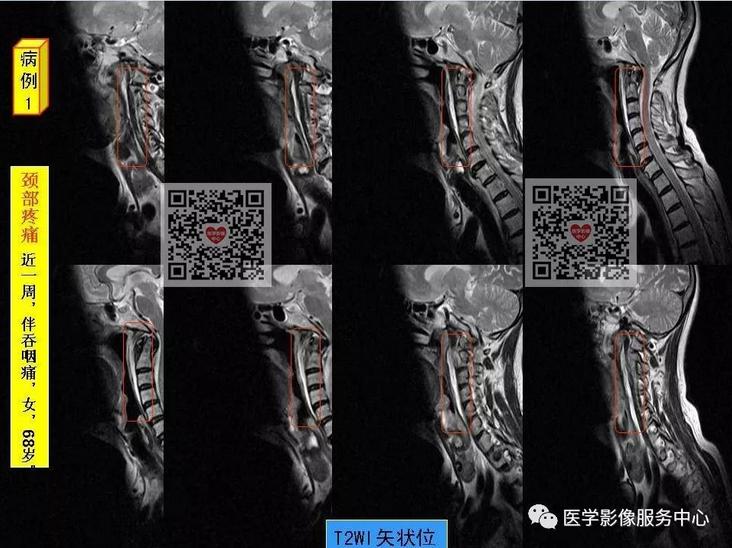

颈椎前缘的条状高信号影,终于知道是什么啦!

颈椎前缘的条状高信号影,终于知道是什么啦~~